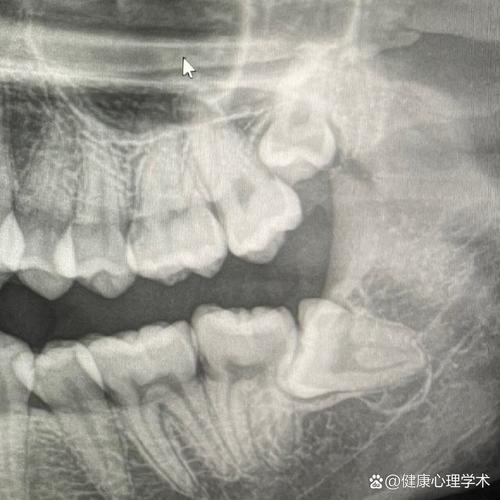

(图片来源网络,侵删)- CBCT(锥形束CT): 这是种植牙、复杂根管治疗、正畸前检查的必备设备,能360度三维成像,精准判断牙槽骨情况、神经血管位置,大大提高手术的安全性和成功率,普通诊所通常没有这种设备。